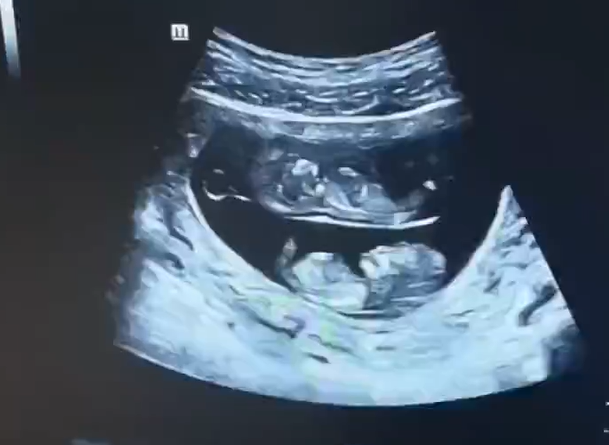

9月3日,河南的一位孕妇妈妈晒出了一对双胞胎宝宝的B超照片,简直逗笑了一群人!这对宝宝的B超图画风有点不一样哦。

首先,让我们来欣赏一下这对萌萌哒的双胞胎?;嫔希辛娇疟ΡΦ男∧源?,一颗在上面,一颗在下面,就像是他们自己在母亲的肚子里订了上下铺一样。当这张照片被晒出后,网友们纷纷惊呼:“原来双胞胎还有上下铺啊,还以为都是大通铺!” 看来大家对于双胞胎的构造有了全新的认识!